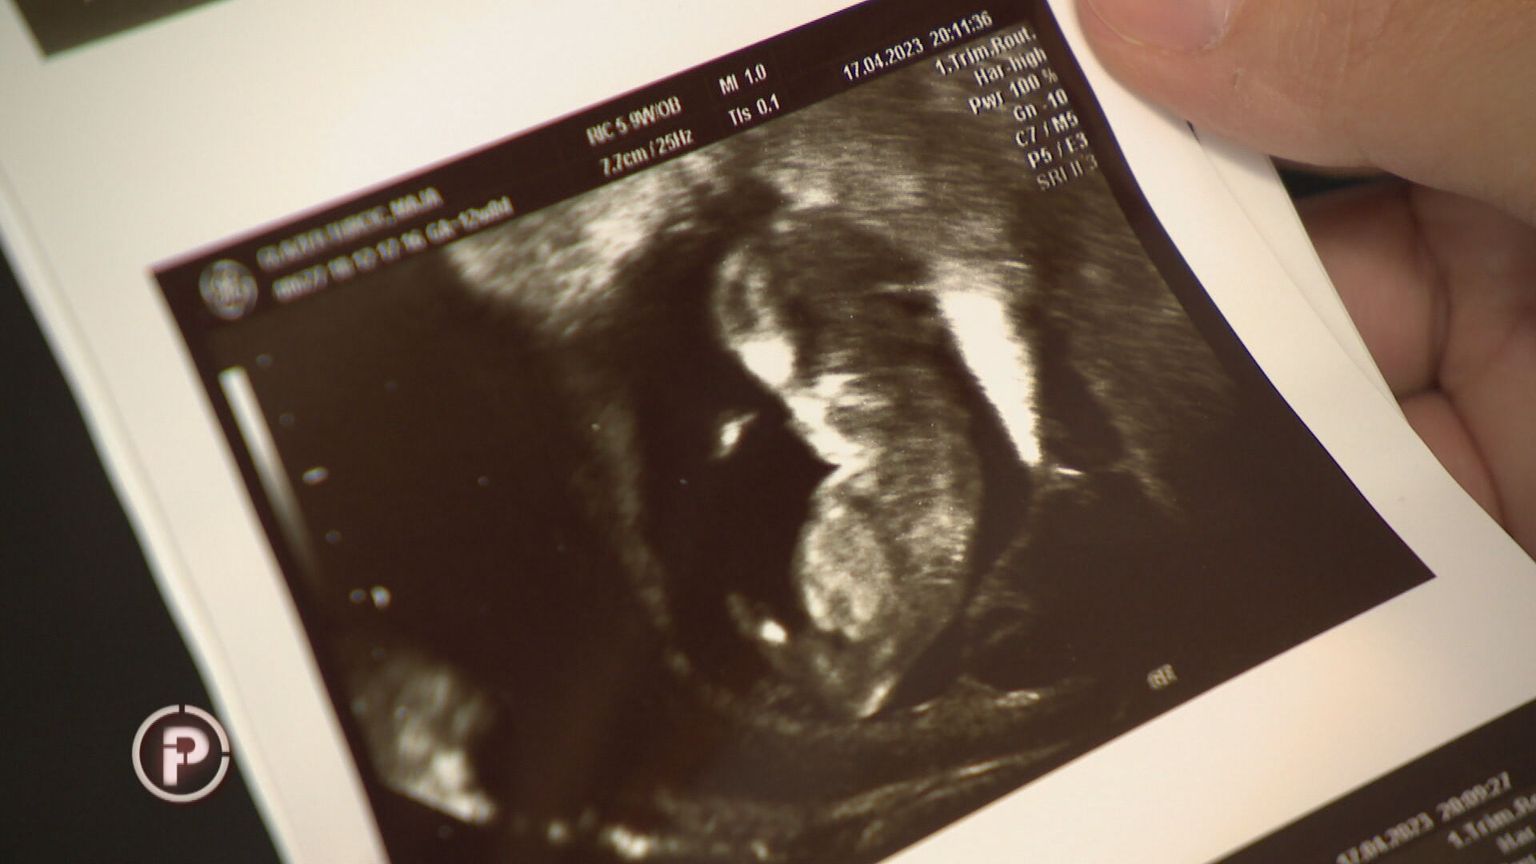

Specijalizantica na UZV-u nije vidjela fetus pa trudnici dala lijek koji se daje nakon spontanog pobačaja: Nakon dva tjedna uslijedio je šok

• Slučaj u Petrovoj bolnici - 2 Foto: Provjereno